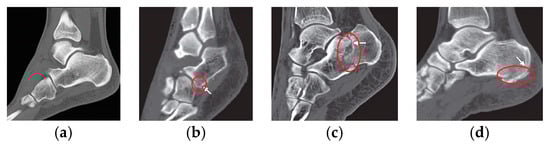

- Bone structure is detected as a fracture,

- The fracture in the image is too similar to the bone structure, so it is not recognized as a fracture.